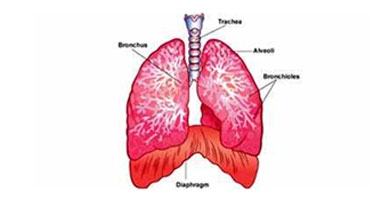

قصبة هوائية ويكيبيديا

جهاز تنفسي ويكيبيديا

ما وظيفة الرئتين بجسم الإنسان اليوم السابع

وظائف الرئتين الرئة البشرية البنية الوظيفة الدواء 2020

موضوعات علمية من الخطب الموضوع 280 الرئتين موسوعة النابلسي للعلوم الإسلامية

أين تقع الرئتين في جسم الإنسان موضوع